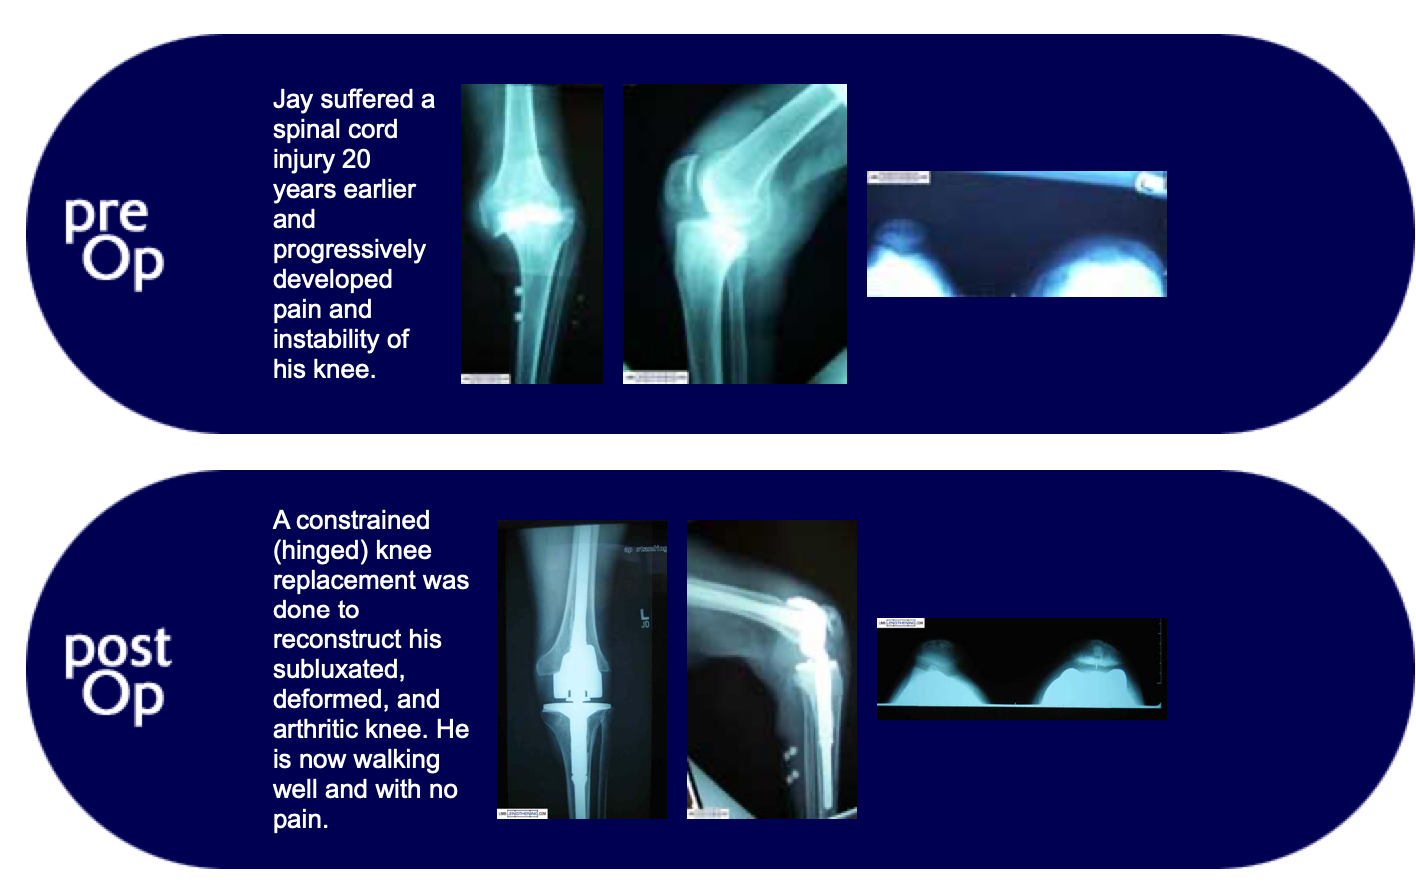

Jay suffered a spinal cord injury 20 years earlier and progressively developed pain and instability of his knee. A constrained (hinged) knee replacement was done to reconstruct his subluxated, deformed, and arthritic knee. He is now walking well and with no pain.